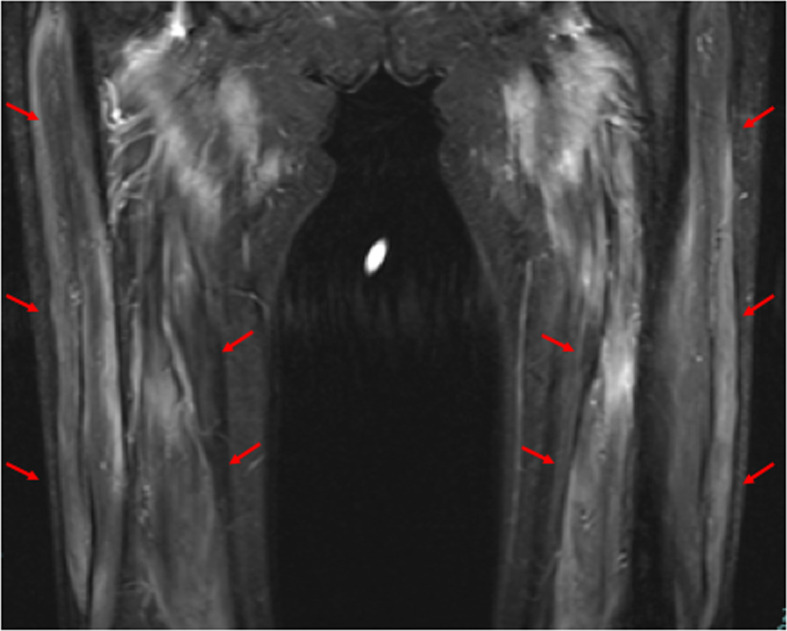

Case: A 76-year-old woman presented with a 4-month history of acute progressive limb muscle weakness and dysphagia. Blood examination revealed significantly elevated creatine kinase (CK) (3472 U/L) and SRP antibody positivity. The patient was near-bedridden and required alternative nutrition. She was treated with oral prednisolone and intravenous immunoglobulin. Rehabilitation therapy was initiated after confirming the decline in CK levels. She started with exercises on the bed and exercise load was gradually increased. Videofluoroscopic swallowing study showed severely weakened pharyngeal contractions and aspiration. Her symptoms improved slowly. She started transferring to a wheelchair after 2 months, gait training using parallel bars after 4 months, and was administered a paste diet once a day after 5 months. Rituximab was administered as additional treatment. Thereafter, the patient started gait training with a walker. The oral paste diet was increased to three times per day after 7 months, and a regular diet was adopted after 9 months. After 11 months, she was discharged home after achieving modified near independence in all activities of daily living.